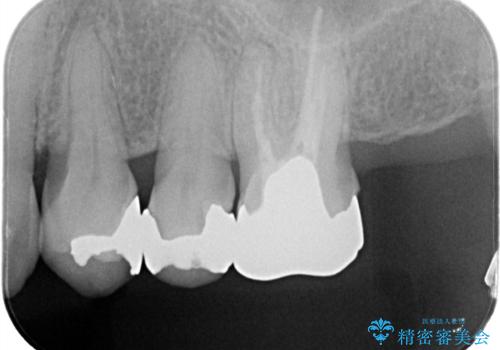

- 左上の4番目と5番目の歯(小臼歯)に入っている銀歯を白くしたいという主訴でご来院されました。

診査の結果、長年使用されていたメタルインレーは経年劣化により適合が悪くなっており、金属の溶け出しによる歯肉の変色や、内部での虫歯再発のリスクも懸念される状態でした。そこで、金属を一切使用しないメタルフリー治療として、耐久性と審美性に優れたセラミックインレーへのやりかえをご提案しました。

治療ではまず、古いメタルインレーを慎重に除去し、内部のわずかな虫歯を取り除いてから形を整えました。